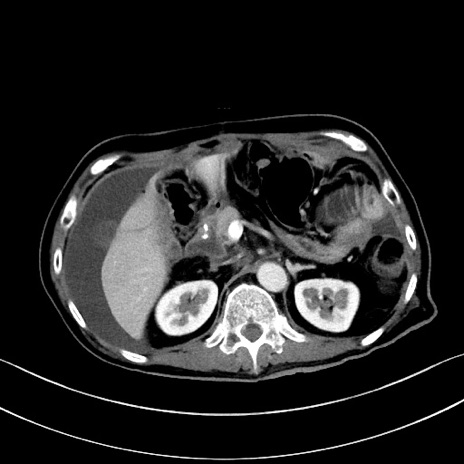

症例

冠状断像

【症例】60歳代男性

【主訴】嘔吐

【現病歴】胃癌にて胃全摘後。食思不振が悪化し、夜中に嘔吐することがある。

【既往歴】胃癌、胃全摘、脾摘、胆摘後

【データ】WBC 5900、CRP 10.56